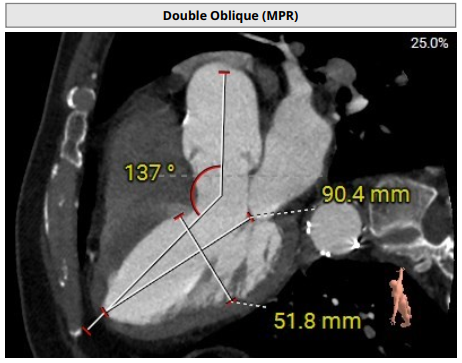

术前评估

术前影像评估提示,患者为典型三叶瓣结构,瓣窦分布均匀,无明显钙化,主动脉瓣环直径29.3mm,左室流出道直径30.6mm,STJ直径37.8mm,升主动脉直径40.5mm,双侧冠脉开口高度充足(左冠17.0mm,右冠27.6mm),无冠脉阻塞风险,左室-主动脉夹角137°,存在一定同轴性挑战。

CTA评估(上下滑动查看更多照片)